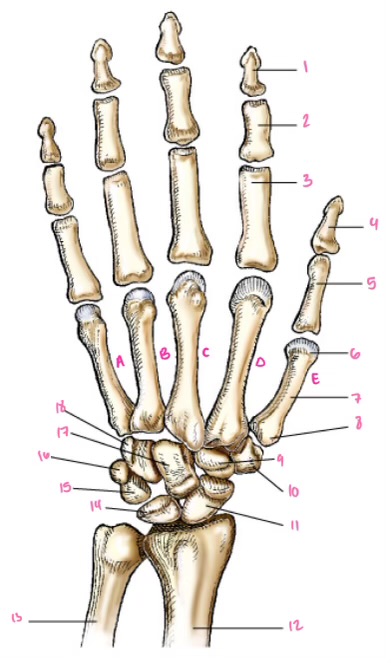

1

1

2

2

3

3

4

9

5

10

6

11

7

14

8

15

9

16

10

17

11

18

1

13

2

14

3

15

4

16

5

17

6

18

7

19

8

20

9

7

22

8

23

9

24

10

25

11

26

13

27

14

28

15

29

16

30

17